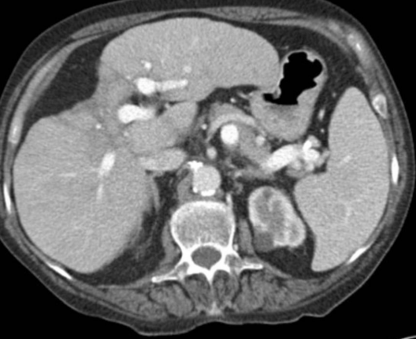

肝硬化中的纤维化较大范围集中时称为融合性纤维化,多见于进展期肝硬化,主要见于酒精性肝硬化。融合性纤维化形态上分为斑片状和肿块状,而肿块状病灶可能为误诊为恶性。CT 上表现为低密度,常累及肝左内叶和右前叶,而尾状叶较少累及。由于纤维组织收缩牵拉,邻近肝体积缩小,肝包膜凹陷(见于 90% 融合性纤维化中),病灶内胆管亦可扩张。MRI 上表现为 T1WI 低信号、T2WI 高信号,信号均匀,增强后呈动脉期无或轻度强化,后呈持续性强化。

肝融合性纤维化,肝硬化背景,增强后肝 S4 段相对稍低密度,邻近肝包膜凹陷。